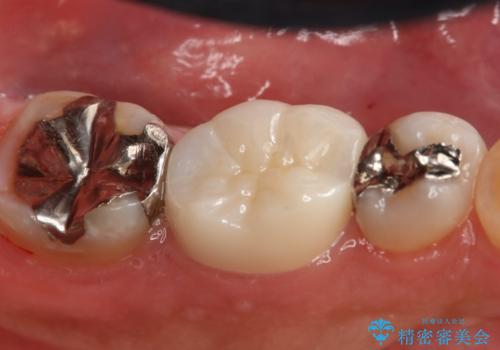

- 左下6番の銀歯が不適であったためやり変えを勧めたところセラミックでの治療を希望された患者様です。

切削量などを考慮し、フルジルコニアクラウンでの治療を選択しました。

う蝕が深く切削量が多くなりましたが痛みなどは起きなかったので、予定通りフルジルコニアクラウンでの治療で進めました。